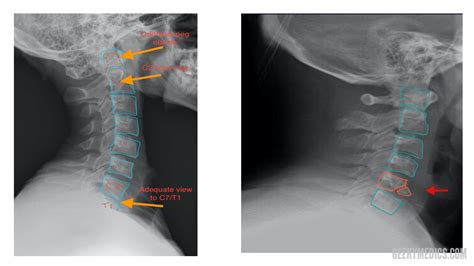

A cervical spine X-ray is a non-invasive diagnostic test that uses electromagnetic radiation to create images of the seven vertebrae located in the neck. These vertebrae, labeled C1 through C7, support the weight of the skull and facilitate head movement. When a radiologist or physician reviews these images, they are looking for specific markers of skeletal integrity.

A Normal Cervical Spine X Ray is characterized by several key features that signify a healthy alignment and bone structure:

• Proper Alignment: The vertebrae should form a smooth, gentle curve known as the lordotic curve. A "straightened" spine, often caused by muscle spasms, can indicate an underlying issue.

• Bone Integrity: The vertebrae should show no signs of fractures, chips, or abnormal bone loss.

• Joint Space: The spaces between the vertebrae (where the discs reside) should be uniform. While X-rays cannot show discs directly, a narrowing of the space can suggest disc degeneration.

• No Foreign Bodies or Lesions: There should be no abnormal growths, tumors, or metallic fragments visible in the soft tissue or bone structure.